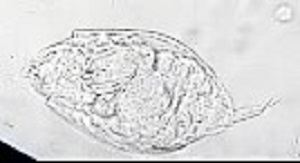

A 10-year-old female patient from Argentina was taken to the hospital by her parent with complaints of “not feeling well.” A urine sample was collected and examined as part of the routine checkup. Microscopic examination of the urine sediment using the 40x objective lens revealed the following: 0-1 WBC and 0-2 RBC per field and a motile organism shown in the video that was sent to the DPDx team for identification. Still images of the organism were made by capturing screenshots at different points of the video (Figures A – C). What is your diagnosis? Based on what criteria?

Figure A